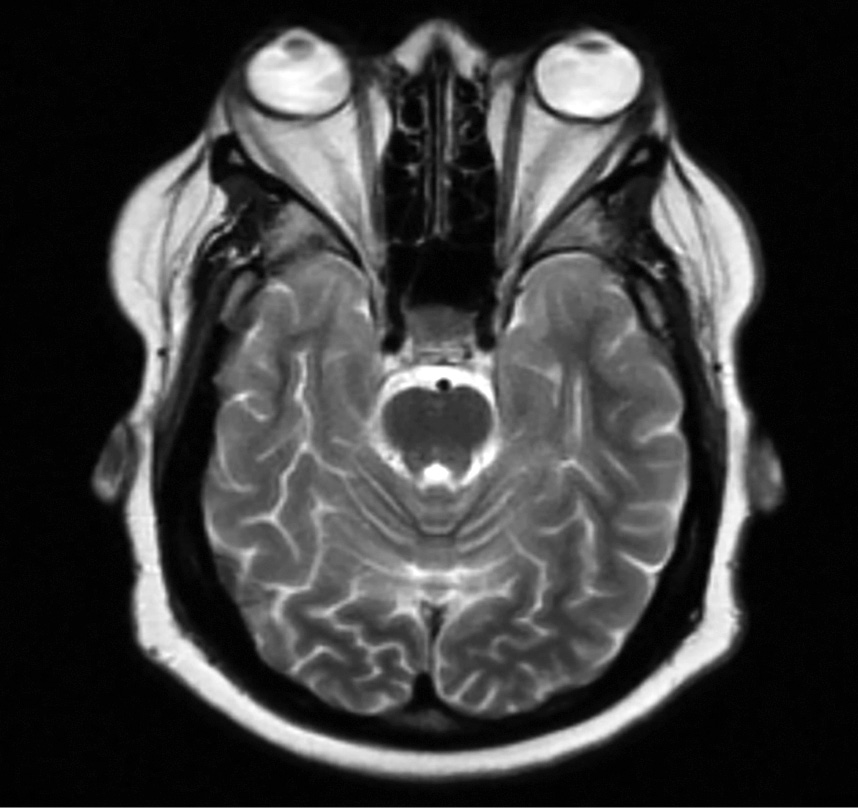

1. Рисунок 1. Билатеральный экзофтальм по данным магнитно-резонансной томографии у пациента с синдромом Кушинга [5] | |